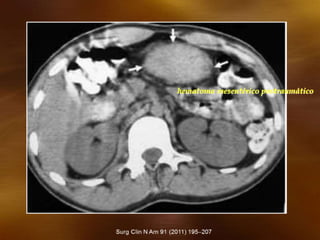

TC axial con contraste

hematoma mesentérico postraumático